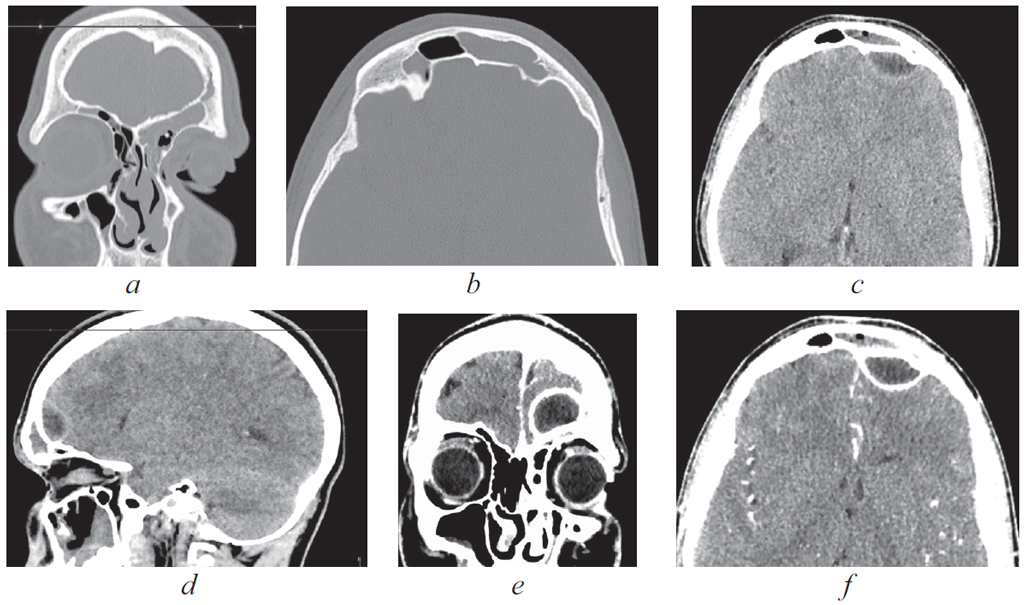

04.06.2021 выполнена мультиспиральная компьютерная томография (МСКТ) ОНП (рис. 1): определяется субтотальное снижение пневматизации левой половины лобной пазухи, задняя ее стенка сохранена, нельзя исключить щелевидные истончения. Затенение лобно-носового кармана слева, клетки решетчатого лабиринта слева частично затенены, деструкции в области переднего основания черепа убедительно не прослеживается. Отмечается пристеночное снижение пневматизации с уровнем жидкости в левой верхнечелюстной пазухе. Округлое новообразование в правой верхнечелюстной пазухе — киста. Пневматизация пазухи клиновидной кости, клеток сосцевидных отростков и барабанных полостей не нарушена.

Рис. 1. Мультиспиральная компьютерная томография околоносовых пазух и головного мозга от 04.06.2021: коронарная (а) и аксиальная (b) проекции в режиме skull, субтотальное затенение левой лобной пазухи, костная деструкция отсутствует; аксиальная (c) и сагиттальная (d) проекции в режиме brain, эпидуральная эмпиема левой лобной области головного мозга; коронарная (е) и аксиальная (f) проекции в режиме brain с контрастным усилением. Эпидуральная эмпиема левой лобной области головного мозга. Отчетливо прослеживается капсула

Fig. 1. Multispiral computed tomography of the paranasal sinuses and brain from 04.06.2021: coronal (а) and axial (b) projections in the protocol of the skull, subtotal shading of the left frontal sinus, no bone destruction; axial (c) and sagittal (d) projections in the brain mode, epidural empyema of the left frontal area of the brain; coronary (е) and axial (f) projections in brain mode with contrast enhancement. Epidural empyema of the left frontal region of the brain. The capsule is clearly visible

04.06.2021 выполнено МСКТ головного мозга: определяется наличие очага гнойного воспаления, исходящего из левой лобной пазухи и отграниченного от вещества мозга капсулой. Наличие двух очагов малого размера («отсевы»), менее 1 см, с признаками формирующейся капсулы. Отмечается зона отека мозгового вещества между очагами.